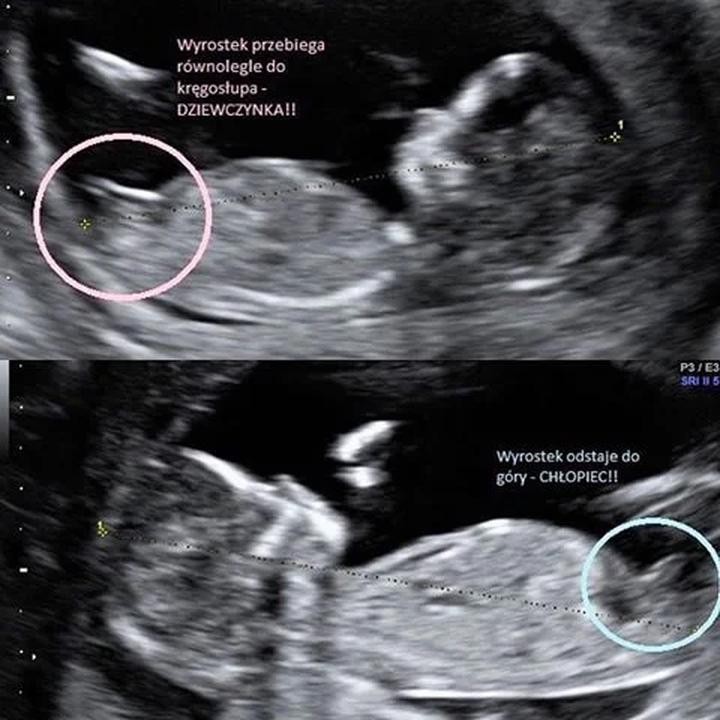

Przyczyny błędnych diagnoz płci podczas USG mogą być dość zróżnicowane. Czasami, gdy maluch leży w niewłaściwej pozycji, diagnoza staje się strzałem w ciemno. Dodatkowo, pępowina potrafi zmylić, udając genitalia. A co, jeśli lekarz korzysta z przestarzałej aparatury oraz ma niewielkie doświadczenie? W takich sytuacjach problemy kumulują się, prowadząc do zabawnych, acz nieładnych momentów, gdy z całkowitą pewnością ogłasza się całkowicie niewłaściwą płeć.

Nie ma sensu się oszukiwać: ułożenie dziecka stanowi klucz do rozwiązania zagadki dotyczącej jego płci. Małe marzyciele mogą wcale nie chcieć rezygnować z wygodnej pozycji, co prowadzi do frustracji zarówno dla lekarza, jak i dla rodziców. Czasami pępowina robi psikusa, zasłaniając płeć, co prowadzi do trafnych przewidywań, że „jest szansa na syna, ale kto wie, co wydarzy się podczas porodu!”. Do tego dochodzą czynniki wpływające na dokładność wyników, takie jak doświadczenie lekarza oraz używana aparatura. Dobrej jakości USG dostarcza klarownego obrazu, ale nawet najlepszy sprzęt potrafi czasem „widzieć” jak pijany żółw!